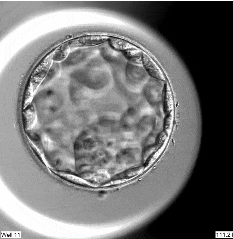

显微镜下的它们,不仅是生命的初始模样,更是爱与期盼的结晶,是未来星辰的微光。

在恒温恒湿的胚胎实验室里,我们以近乎艺术般的专注(ISO 9001:2015国际质量体系认证)呵护您的胚胎:从精卵相遇的刹那,到胚胎成长的每一刻,我们“零干扰”的静默守护,让生命在最适宜的环境中悄然绽放。

通过胚胎种植潜能数字化评估技术,我们筛选出最具活力的胚胎;特色囊胚培养技术让囊胚形成率达65%,让您的成功再加一份安心。